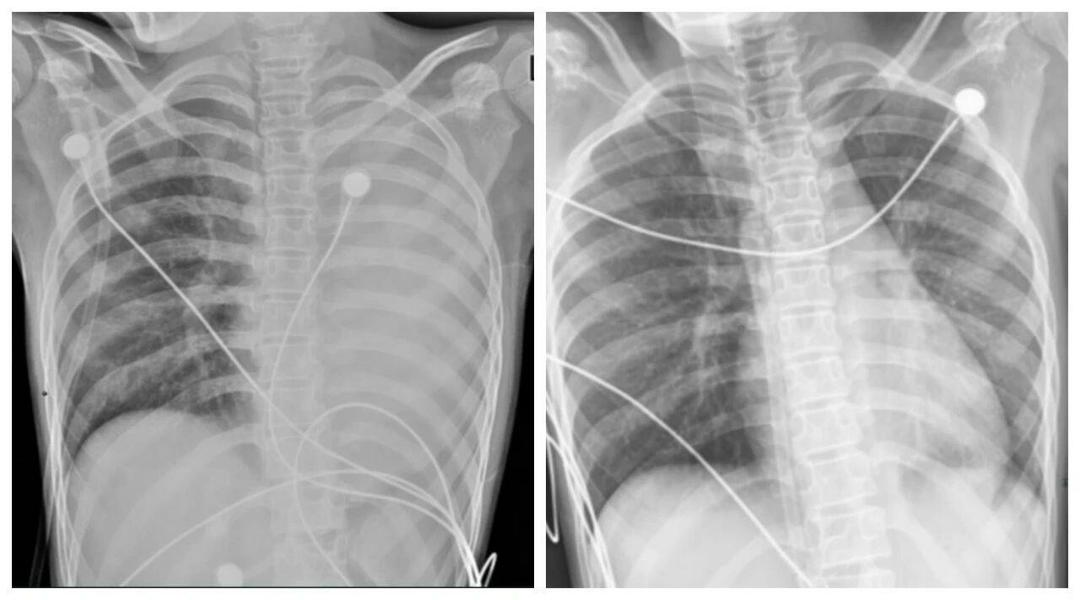

Một bé trai 12 tuổi nhiễm cúm A chủng H3N2, chỉ sau 24 giờ hình ảnh phổi đã xuất hiện tình trạng viêm lan tỏa nghiêm trọng, còn gọi là “phổi trắng”.

Những ngày gần đây, dư luận Trung Quốc đặc biệt chú ý tới một ca bệnh tại tỉnh Hà Nam, Trung Quốc : một bé trai 12 tuổi nhiễm cúm A chủng H3N2 , chỉ sau 24 giờ hình ảnh phổi đã xuất hiện tình trạng viêm lan tỏa nghiêm trọng, còn gọi là “phổi trắng”. Trẻ rơi vào suy hô hấp nặng và chỉ được cứu sống nhờ hệ thống oxy hóa máu qua màng ngoài cơ thể ( ECMO).

Về mặt y khoa, “phổi trắng” không phải phổi biến đổi màu sắc thật mà là hình ảnh X-quang hoặc CT cho thấy vùng viêm, thâm nhiễm chiếm trên 70% nhu mô phổi . Nếu được điều trị kịp thời bằng kháng virus, kháng sinh, rửa phế quản… phần lớn tổn thương có thể hồi phục.